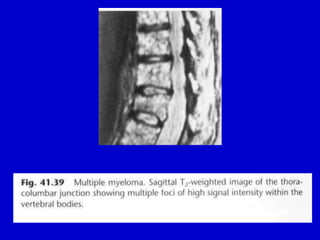

• 44.

• Fig. 41.40 Myelomatosis.Diffuse marrow involvement has resulted in an overall reduction in bone density similar to that seen in osteoporosis. However, the rather patchy nature of radiolucencies should raise the possibility of myeloma.